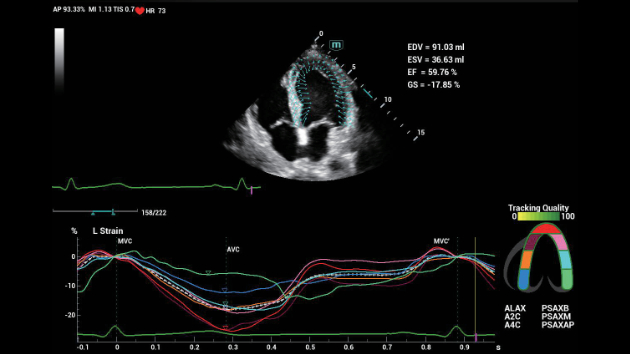

Indipendentemente dalle attività svolte in ospedale o in clinica, oppure se si desidera affinare le proprie capacità nella diagnostica per immagini generale negli ambiti della salute della donna o cardiovascolare, questa serie di soluzioni fornirà potenti strumenti per essere sempre un passo avanti.

Soluzioni di diagnostica per immagini complete con tecnologia ZST+

La piattaforma ZST+ è un'innovazione straordinaria, che rappresenta un'evoluzione nel campo dell'ecografia. Grazie alla trasformazione delle metriche a ultrasuoni dal beamforming convenzionale all'elaborazione basata sui dati di canale, supera la tradizionale limitazione del trade-off tra risoluzione spaziale, risoluzione temporale e uniformità dei tessuti, offrendo una qualità d'immagine eccezionale per infinite soluzioni di imaging con miglioramenti continui.